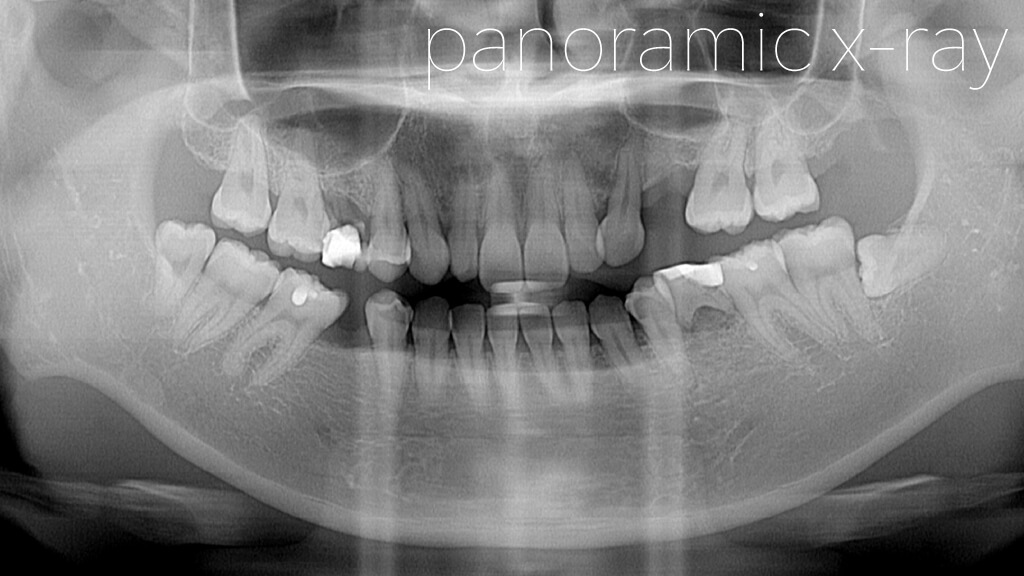

1.術前オルソ

今回の患者さまは、札幌にお住まいの女性です。

先天的に永久歯が欠損している部位があり、本来であれば永久歯に生え変わる部分が、乳歯(E)のまま残っている状態でした。

しかし、その乳歯もすでに機能しておらず、歯ぐきに埋まっているような状態になっていたため抜歯を行うことになりました。

そのため、上下左右に歯が欠損している部分があり、そのスペースをどのように治療するかが大きなポイントとなります。

8.術後オルソ

今回は、上下左右それぞれ1本ずつ、合計4本のインプラントを埋入しています。

上顎については、左右ともに上顎洞(サイナス)までの骨の高さが不足していたため、「Densah® Bur(デンサーバー)」を用いたサイナスリフトを併用しました。

上顎の奥歯の部分は、歯を失った後に骨が吸収されやすく、インプラントを埋入するために必要な骨の高さ(垂直的な骨量)が不足していることがよくあります。

このような場合には、上顎洞(サイナス)という空洞の底を持ち上げて骨を増やす処置である「サイナスリフト」を行い、インプラントを安全に埋入できる骨の高さを確保します。

今回は、Densah® Bur(デンサーバー)という特殊なドリルを使用し、骨を削るのではなく押し広げるように形成することで、骨を温存しながらサイナスリフトを行いました。

これにより、骨への負担を抑えながら、インプラントの初期固定をしっかり確保した状態で埋入することができました。